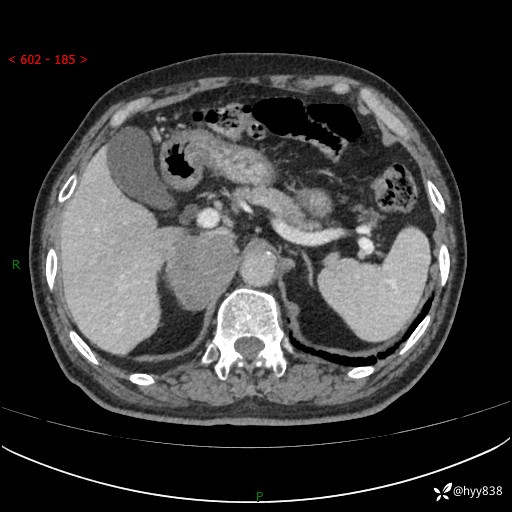

【患者信息】:76岁/男

【主诉】:检查发现右侧肾上腺占位6天

【现病史及既往史】:患者6天前体检发现右侧肾上腺占位,无腰痛,无放射痛,无尿频、尿急、尿痛及肉眼血尿,无畏寒、发热,无恶心、呕吐,今为求进一步治疗,遂来我院就诊,门诊拟“右侧肾上腺占位”收住入院。 起病以来,患者精神、饮食、睡眠可,大小便如常,体力体重无明显变化。

【检查】:肾上腺CT平扫+增强